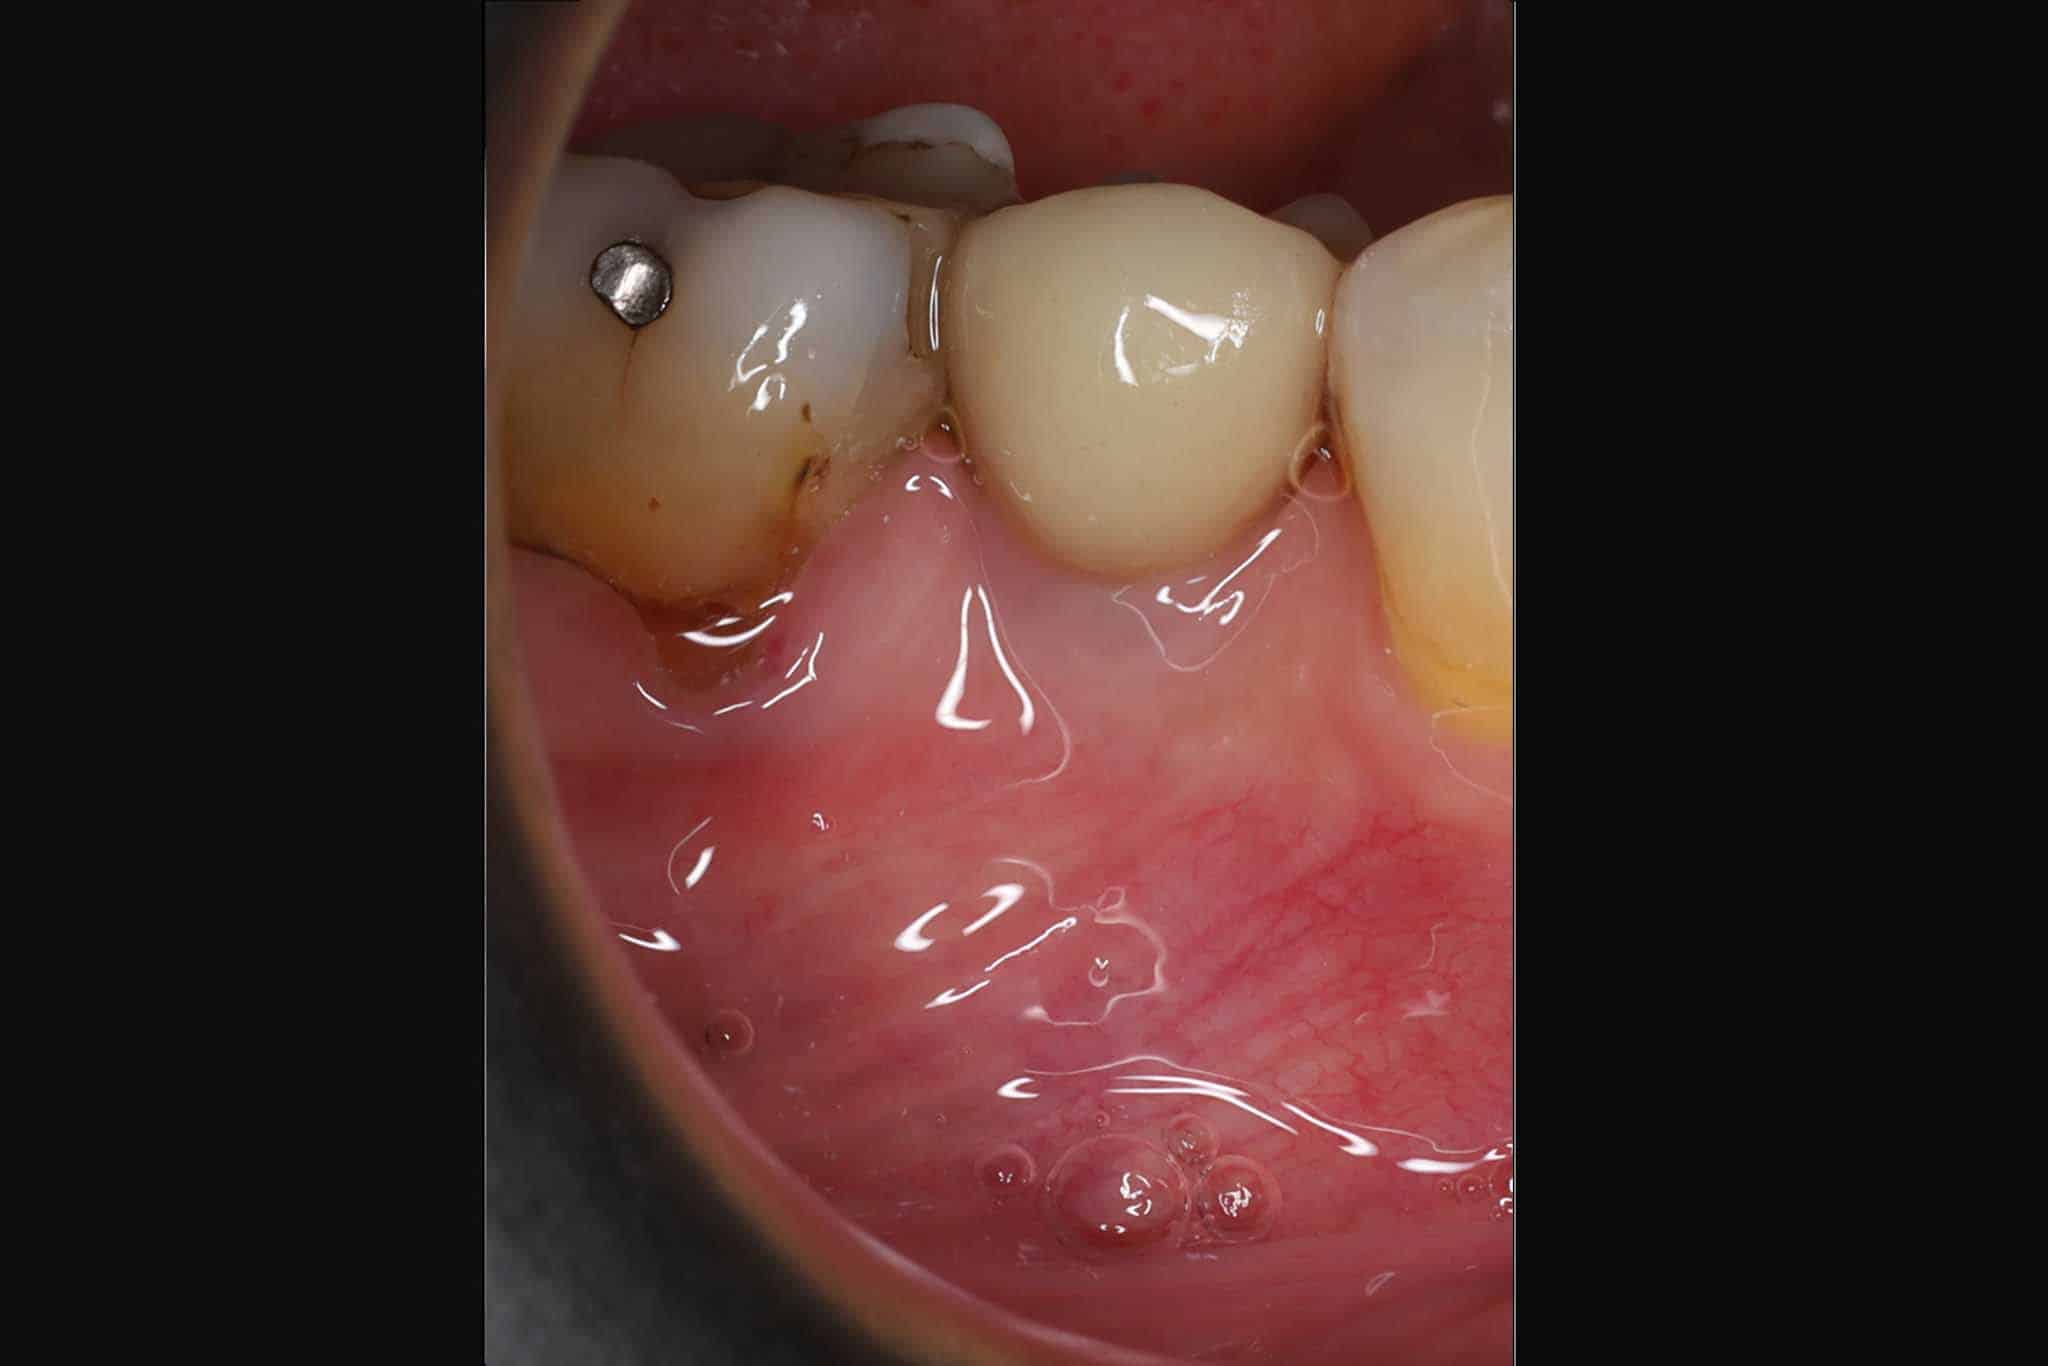

Bildet viser midtre tann som implantat – sammenligning av foto og røntgen.

Før- og etterbilder av tannimplantater – Se våre pasientresultater

Bildet viser resultat før og etter tannimplantat.

Resultat av implantatbehandling dokumentert på foto og røntgen.

Resultat etter tannimplantat.